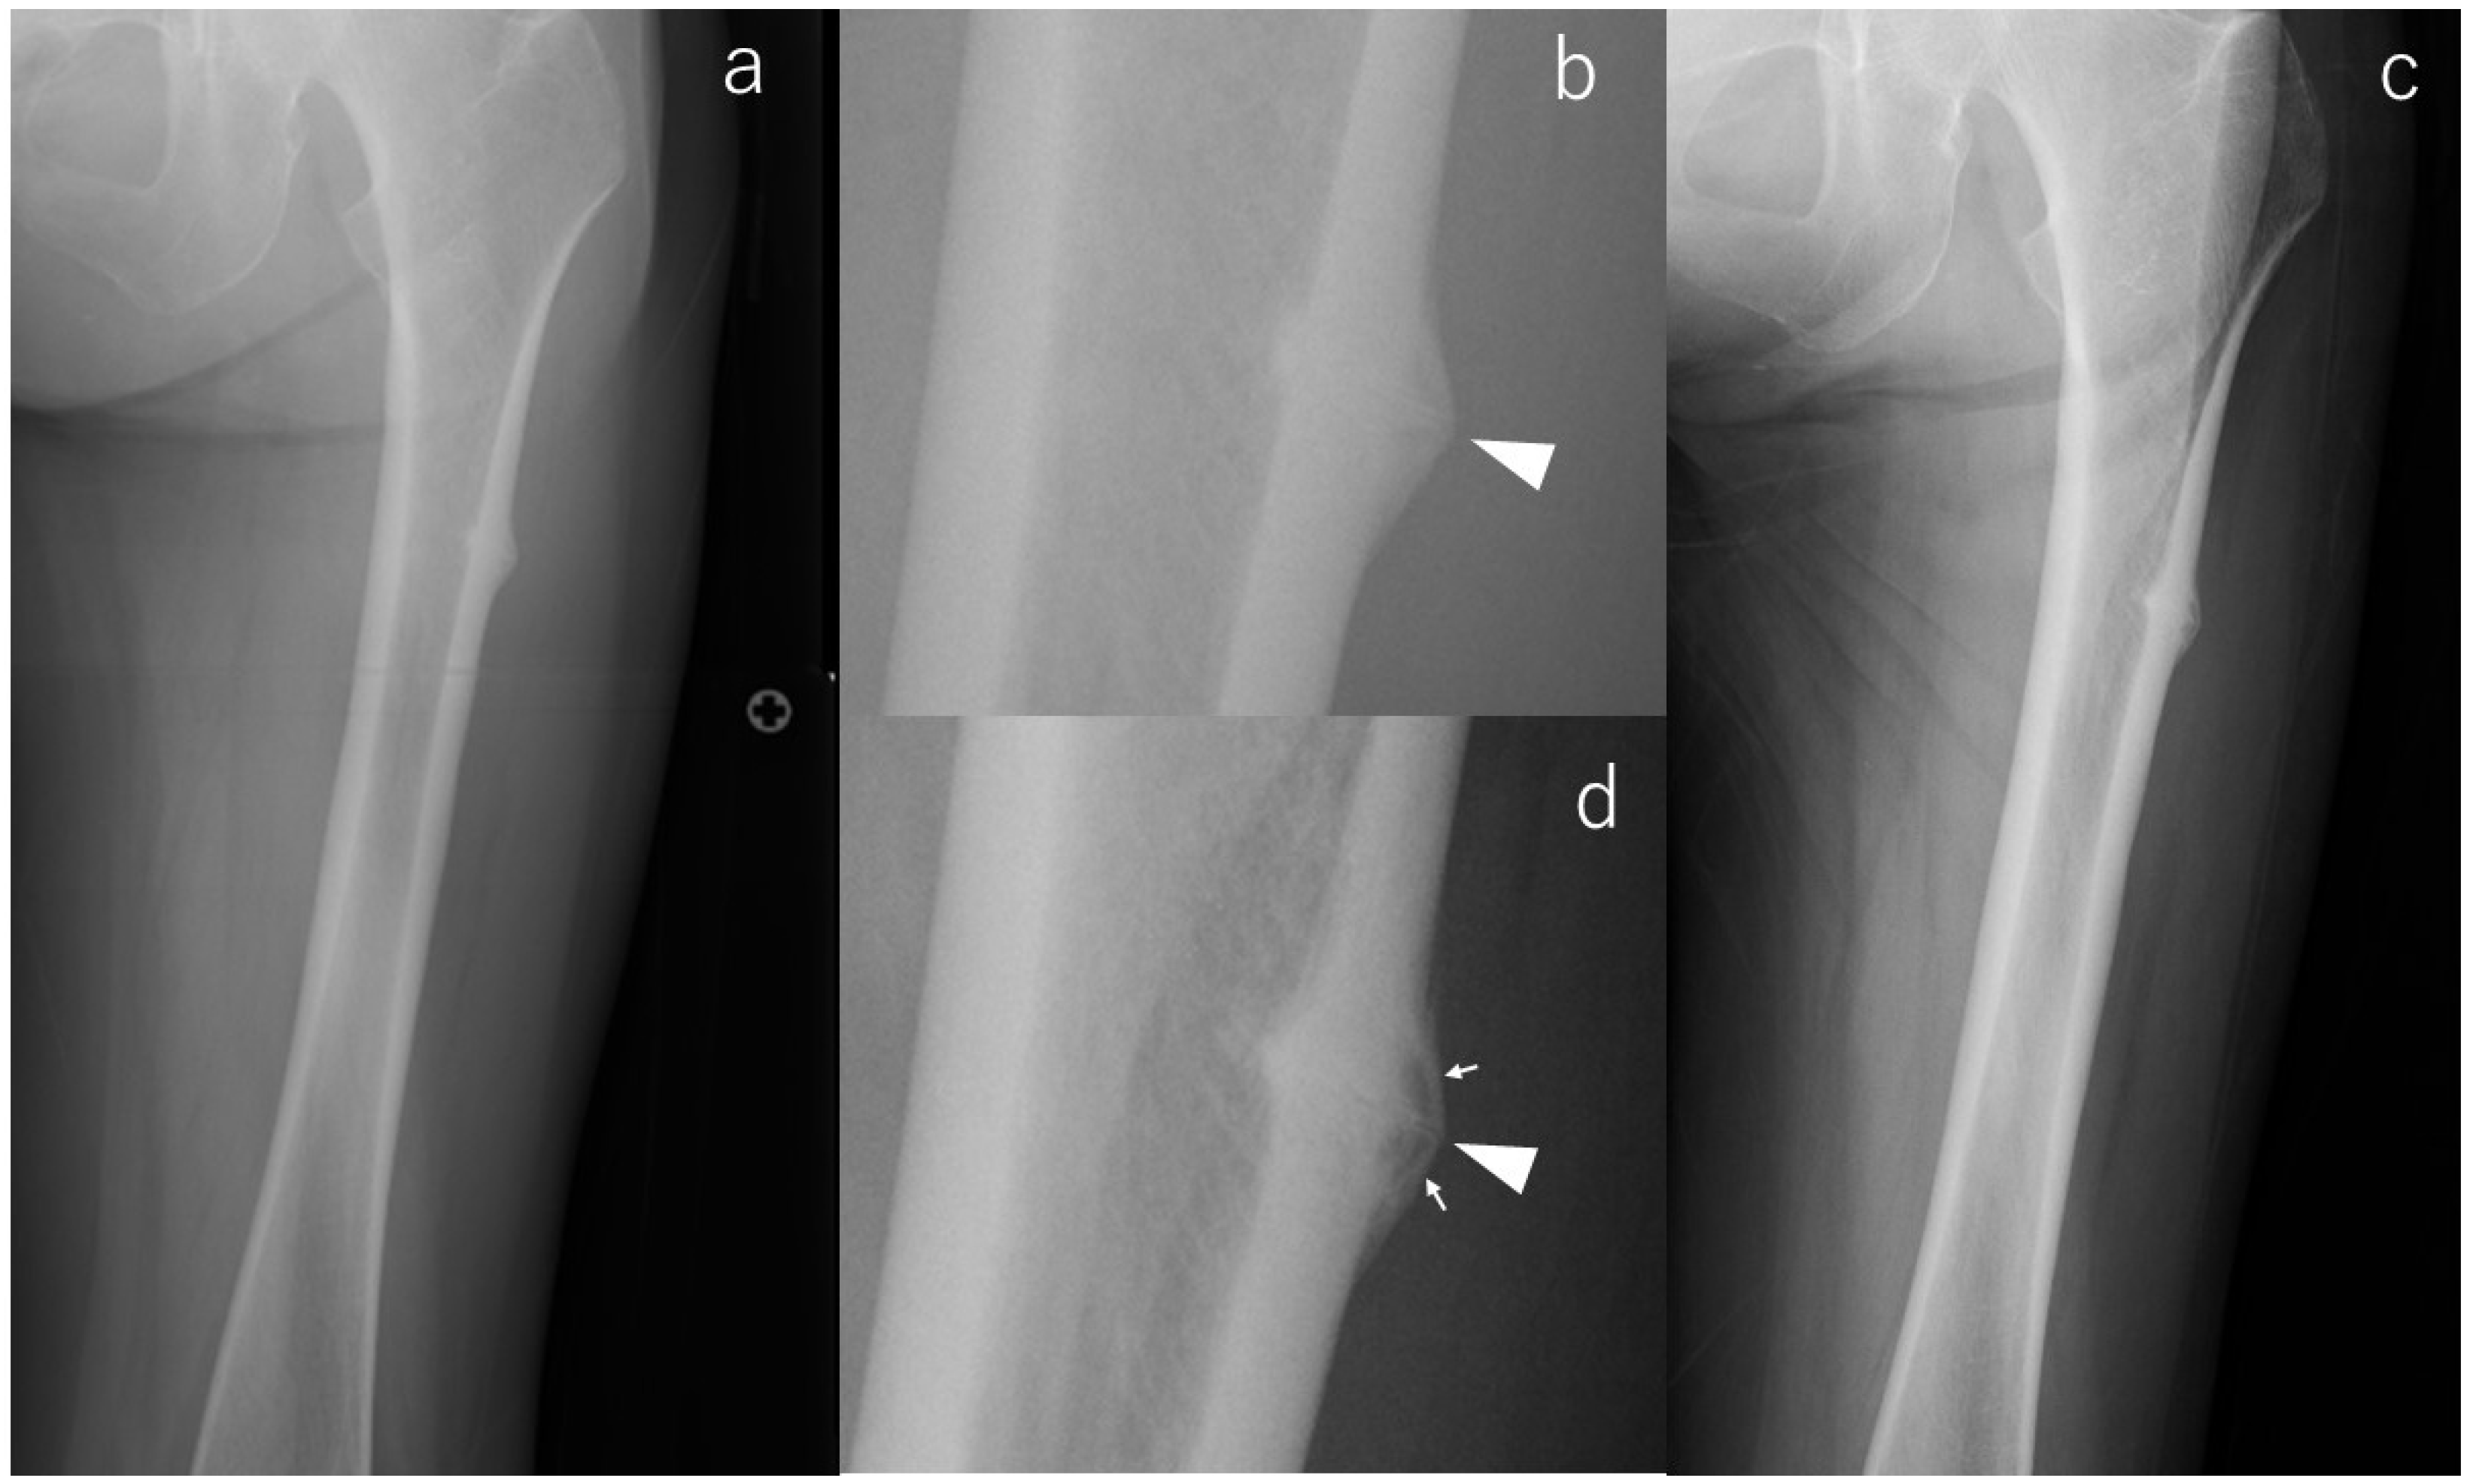

Consistent with the concept that radiographic morphology can progress silently, one limb demonstrated clear enlargement of the incomplete lesion, corresponding to case #2 (Figure 1). At baseline, radiographs of the contralateral femur revealed pronounced subtrochanteric lateral cortical bulging accompanied by beaking and a transverse radiolucent line—findings known to represent a higher-risk diagnostic phenotype. Eighteen months later, follow-up imaging showed a marked increase in beaking size and well-defined internal radiolucency, indicating radiographic progression despite the absence of symptoms. Because the patient died from malignancy 18 months after surgery, extended imaging follow-up was not possible.

Figure 1. X-rays of case #2 at various time points. (a): Radiograph at the time of injury, (b): Enlarged image of a; radiolucency running across the cortex (arrowhead), (c): Radiograph at the last observation, (d): Enlarged image of (c); magnified fracture line (arrowhead) and radiolucency in the beak (arrows).